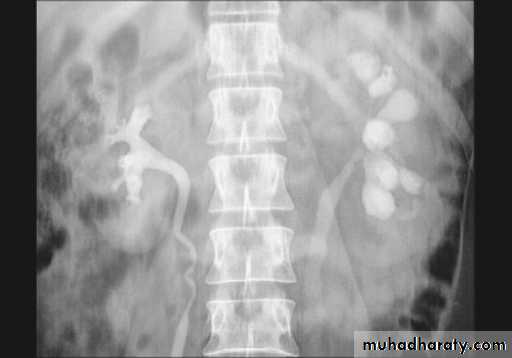

3. After 10 minutes with compression, to get better distention of the pelvis and calyces.

Urinary system